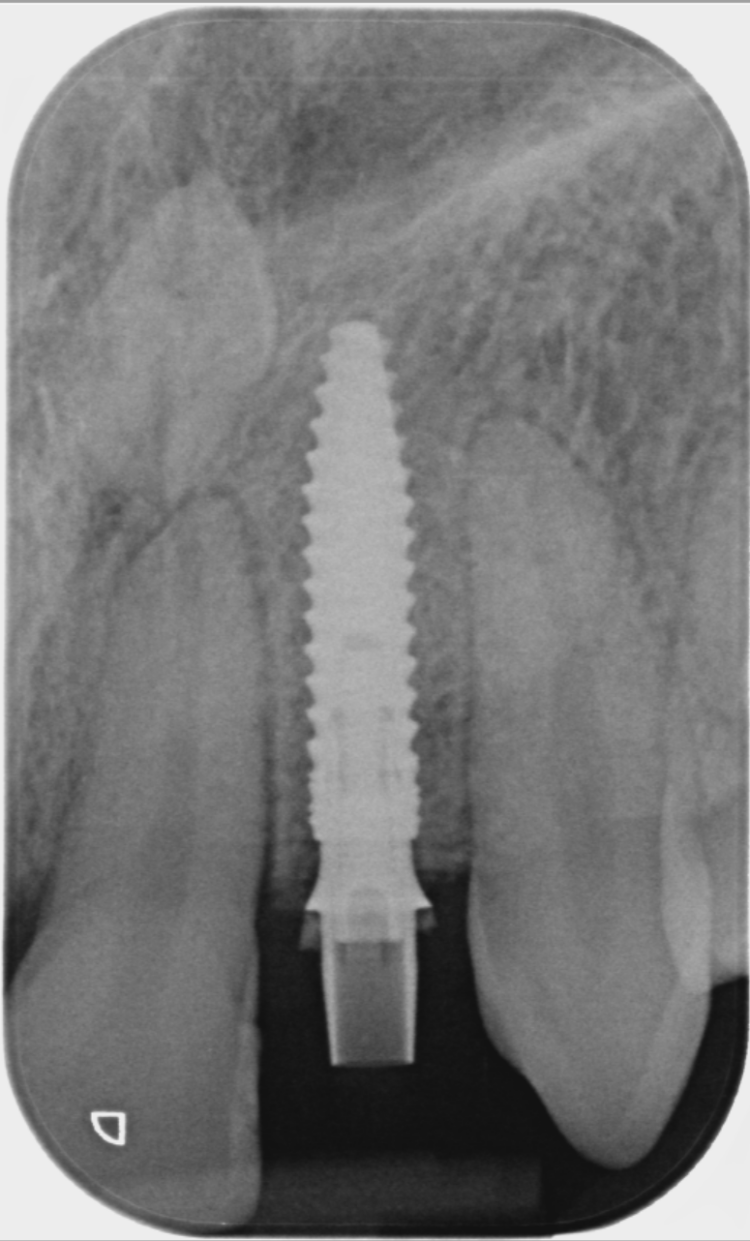

Post-surgical healing and impressions (August 2023)

A week after the surgery, the patient was seen for a healing review, during which X-rays were taken and sutures were removed. After sufficient healing, the patient returned for an impression appointment, where the temporary teeth were removed and scans were taken to fabricate the final crowns.